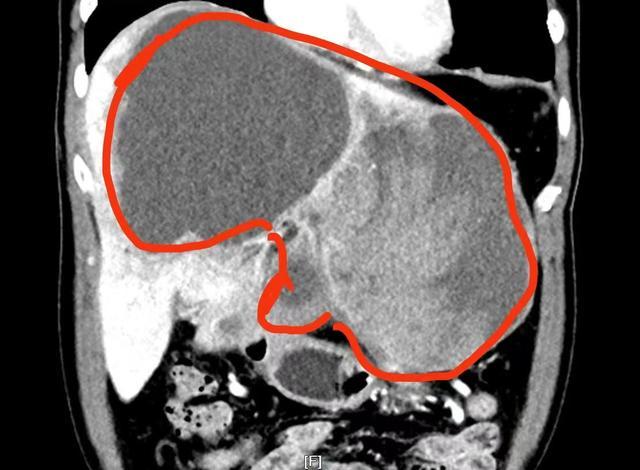

(▲影像资料显示:巨大的肿瘤占据了刘先生整个肝脏的三分之二。)

专家团队一致认为:巨大的肿瘤占据了患者整个左肝以及右肝前叶,手术操作空间极为狭小;加上肿瘤内部出血超过2000毫升,面对血供如此丰富的肿瘤,手术操作必须十分精准,否则极可能引发术中大出血,甚至危及生命;此外,在术前的下肢深静脉血栓筛查中,患者被发现有右下肢静脉血栓。为防止术中、术后出现致命性肺栓塞,介入血管外科医生为他放置了血管滤器。